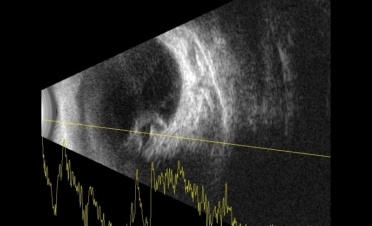

La ecografía permite observar las estructuras del globo ocular cuando la transparencia de la córnea está comprometida o cuando deseamos observar con detalle los segmentos anterior y posterior del ojo.

En ambas pruebas se observaron imágenes compatibles con un desprendimiento de retina:

Imágenes de la ecografía de Fox, un perro de raza Pomerania con desprendimiento de retina en ambos ojos. Se descartaron otro tipo de lesiones oculares. Foto: IVO. (Clicar la fotografía para ampliar)